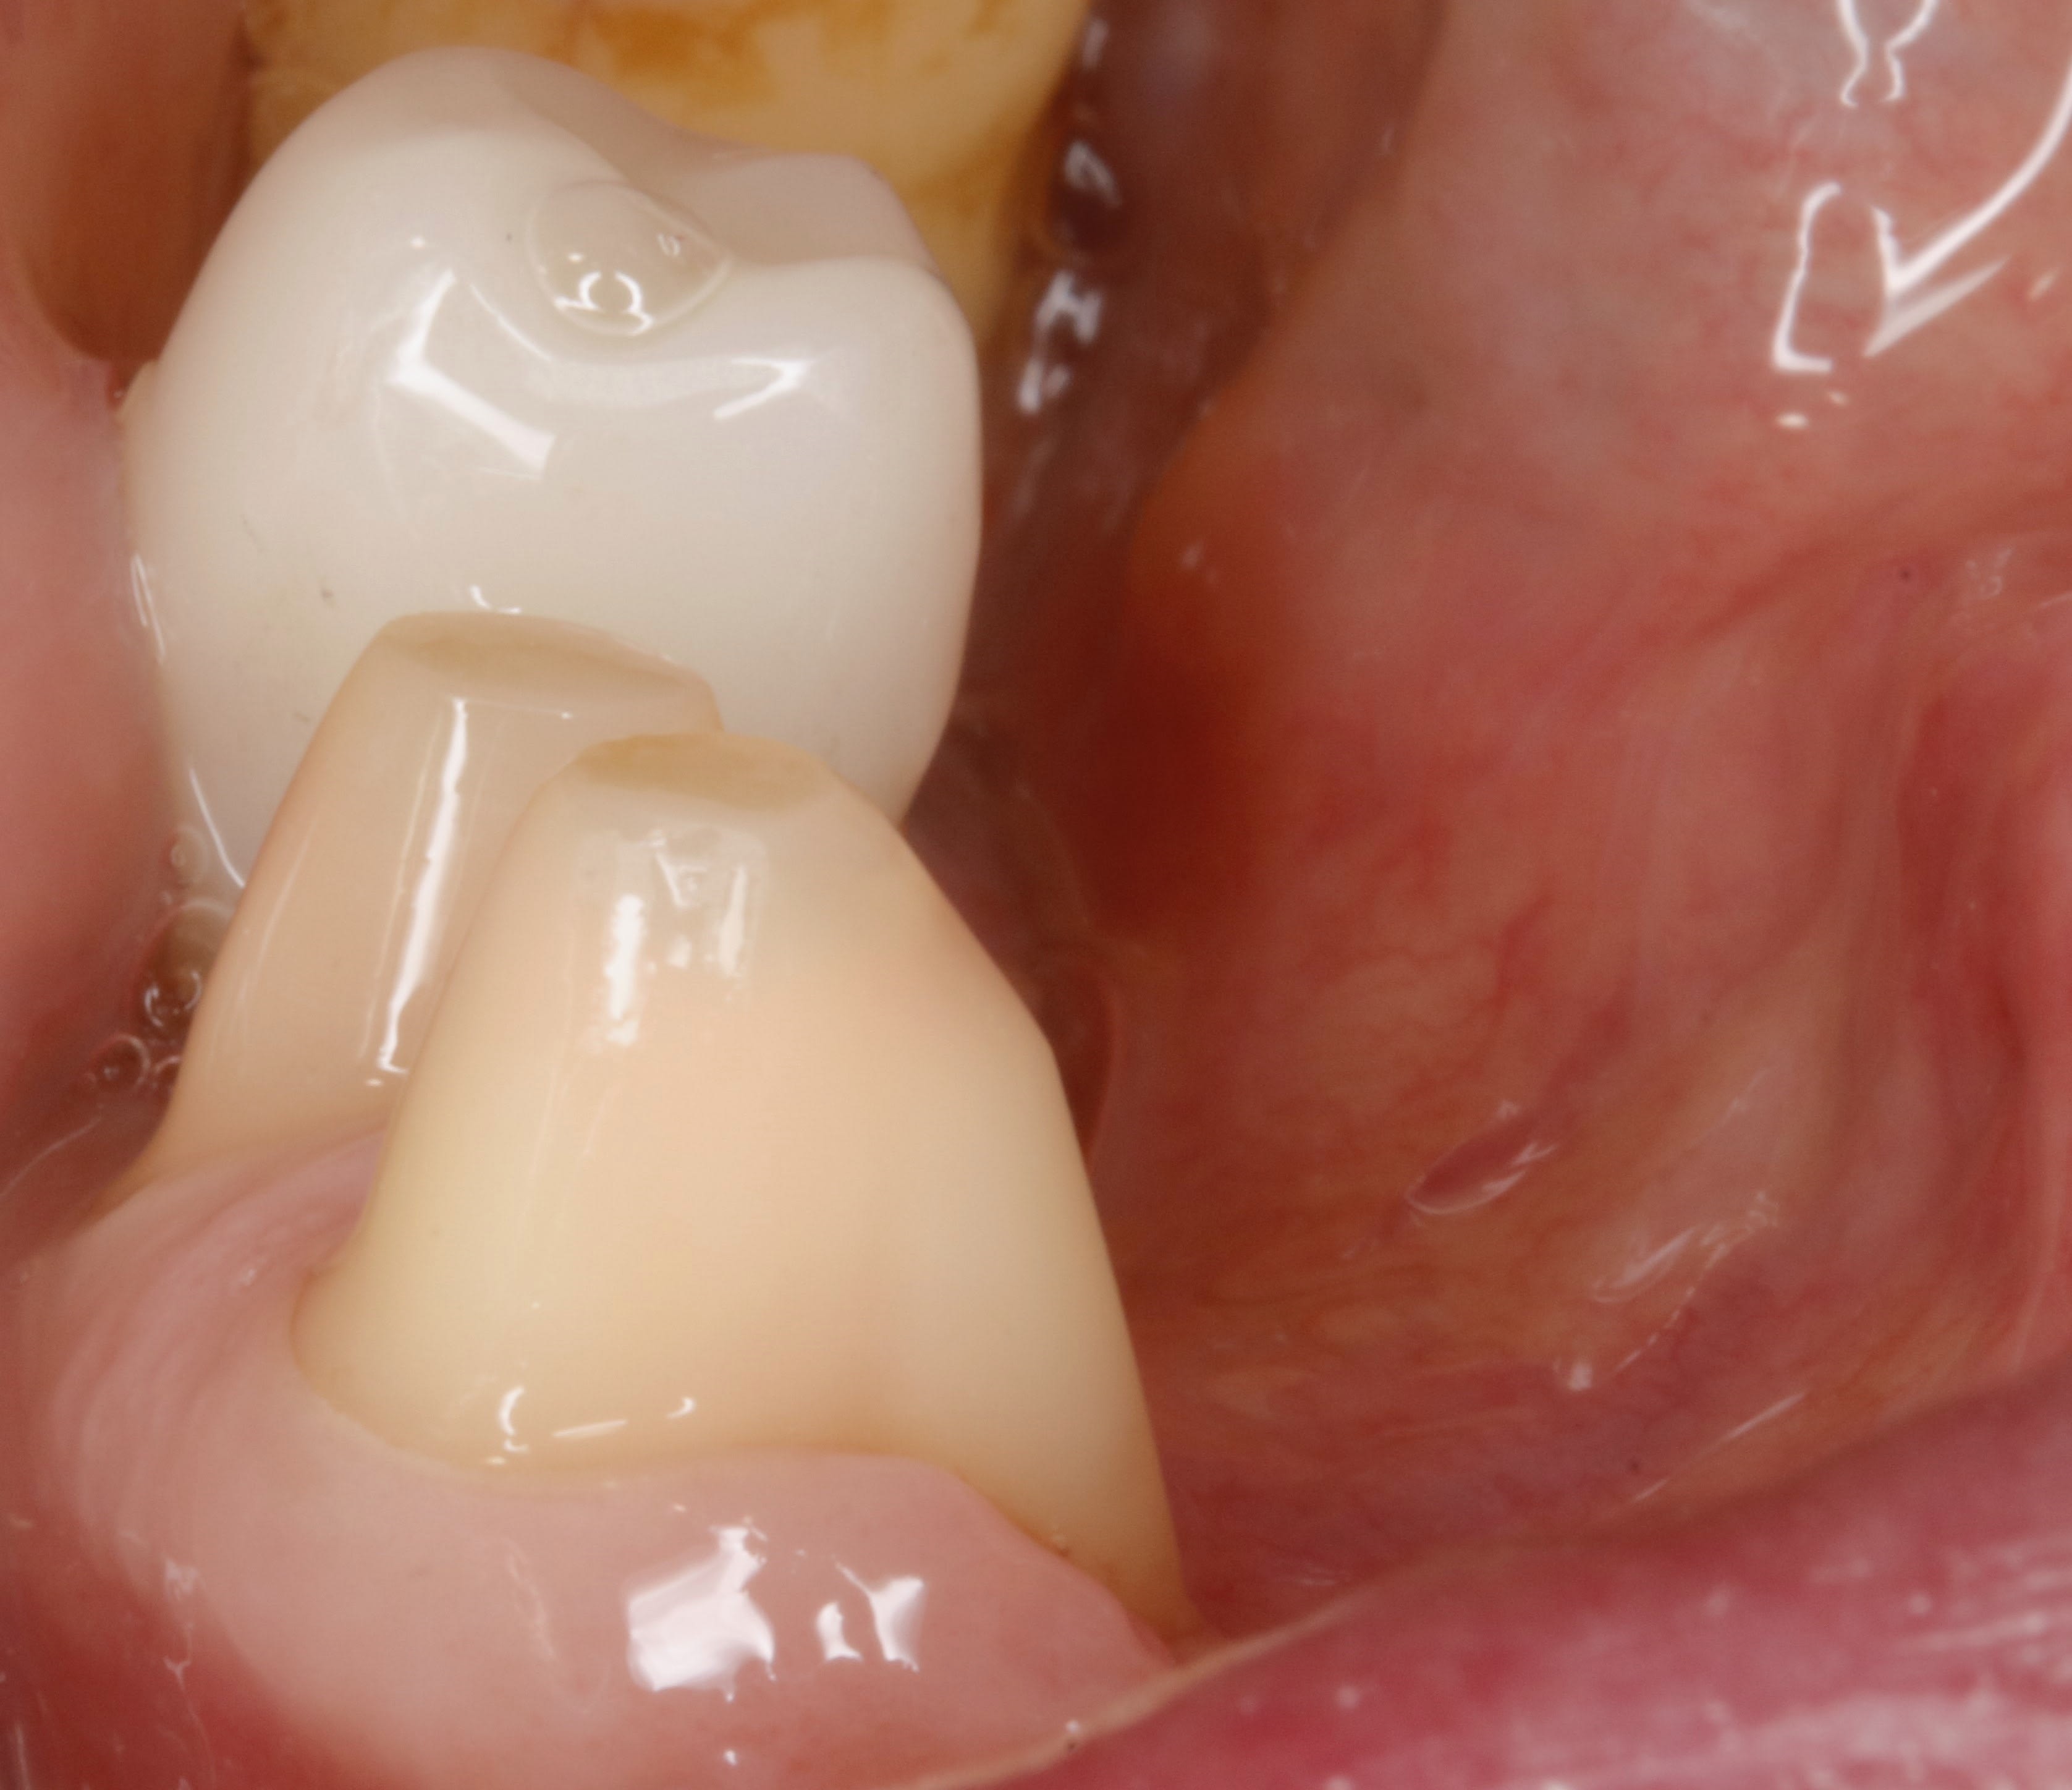

Je pense que j'ai un problème avec mes tailles de moignon sur molaires du bas lorsqu'il n'y a pas assez de hauteur car j'ai 3/4 cas de descellement récurrent. Et ça uniquement, si je ne mets pas d'inlay core. Bien sûr, l'occlusion est vérifiée et me semble ok.

J'ai tout tenté et refait mes CCC : taille plus conique, congé plus large, cuspides plus inclinées, ou carrément plates, fraisage rétentif sur les faces V ou L ..

Bref, je fais tout pour que ma préparation ressemble à des inlay core mais rien n'y fait... ça se descelle une fois par an !!

De plus, tes moignons sont superbes c'est sûr , mais moi quand ils sont super lisses comme les tiens, le light se barre et il n'y a que le putty qui reste sur la préparation lors de l'empreinte, même en polissant mon moignon au Zircate avant l'empreinte.

Ici les préparations sont trop coniques, et 4 tailles c’est 4 agressions pulpaires…

Daryl , n ais pas honte , il y a plein de choses intéressantes dans ta question , et je reprendrais point par point avec mon avis , mais qui n engage que moi , comme d ab .

mais déjà je peut te dire que je n ai pas ton genre de pb , pour une bonne raison évidente , c est que je suis plus vieux que toi :-))

pas que je sois plus fort :-) , mais que j ai donc une clientèle plus âgée que la tienne . donc avec des dents de vieux , déchaussées , pbs paro , ... et donc à hauteur prothétique plus élevée que pour tes patients : tous ces minots qui sont passés par l ortho (ou pas ) avec des hauteurs molaire riquiqui ,..